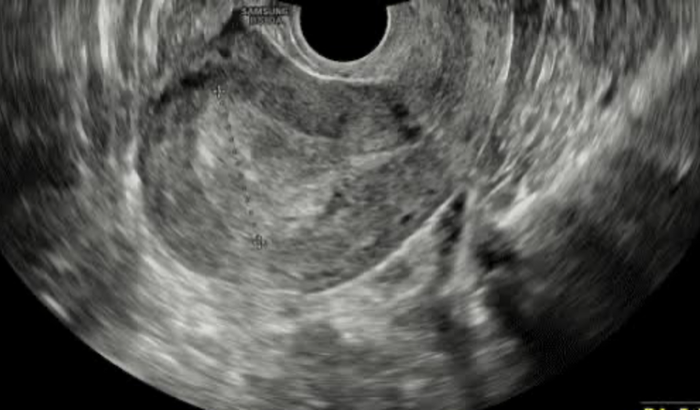

Eu me chamo Rebecca, eu e meus irmãos decidimos criar essa vakinha para levantar um dinheiro para ajudar no tratamento da minha mãe, que foi diagnosticada com um espessamento no endométrio que pode ser algo benigno como também maligno. Minha mãe vai precisar passar por um procedimento cirúrgico que ficou no valor de R$ 5.000,00 incluindo hospital, equipe médica e anestesiata, e como o sus não cobre e essa noticia nos pegou um pouco desprevenidos precisamos da sua ajuda. Qualquer valor já nos ajuda!